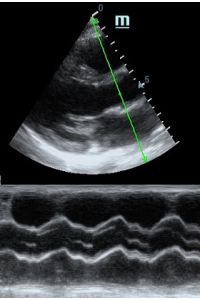

Но как же провести стандартные измерения в М-режиме, если мы его не использовали? На помощь приходит функция Free Xros M – анатомический М-режим. Имея записанную в память прибора видео петлю, мы можем провести линию М-режима в любом месте, при этом корректируя изначально не оптимальный угол.

MAPSE - амплитуда движения латерального кольца митрального клапана, позволяет рассчитать фракцию выброса по формуле EF = 4.8 × MAPSE (mm) + 5.8, очень быстрый и гораздо более точный («прародитель Strain») метод чем широко распространенный метод Teicholtz. В современных приборах можно легко добавить свою формулу при отсутствии ее в стандартном калькуляторе. Главным условием является проведение линии М-режима параллельно стенке левого желудочка в апикальном четырехкамерном сечении, что легко достигается при использовании функции Free Xros.